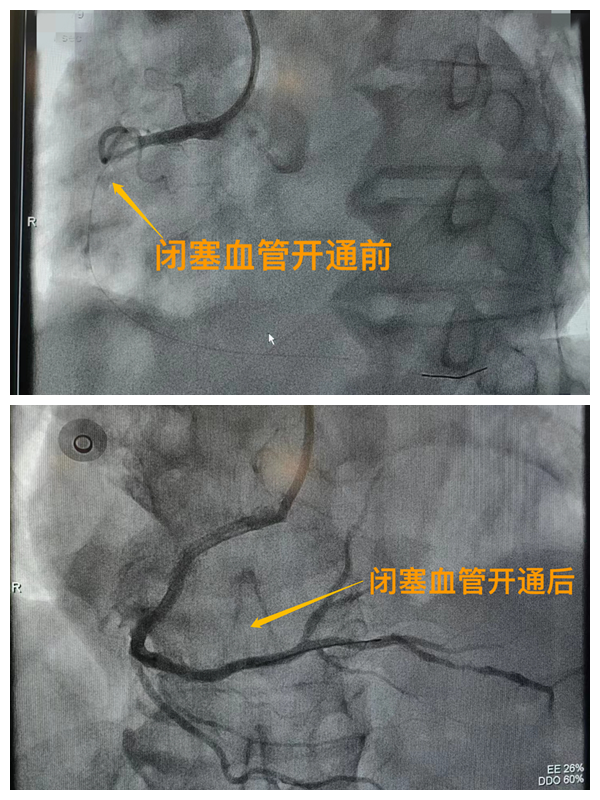

健康科普鏈接

市二院胸痛中心于2021年12月23日通過中國胸痛中心認證,成為國家級胸痛中心,先后開展了冠心病的介入診療、心律失常的心內電生理檢查及射頻消融治療、永久起搏器植入、先天性心臟病的介入封堵及臨時起搏器植入、主動脈內球囊反搏治療等,完成心臟介入手術3000余例。多次創(chuàng)造從入院至行急診介入手術開通血管(入門-導絲通過)30分鐘以內記錄,極大保證了患者的生命安全,提高了預后質量,挽救了眾多急性心梗患者的生命。